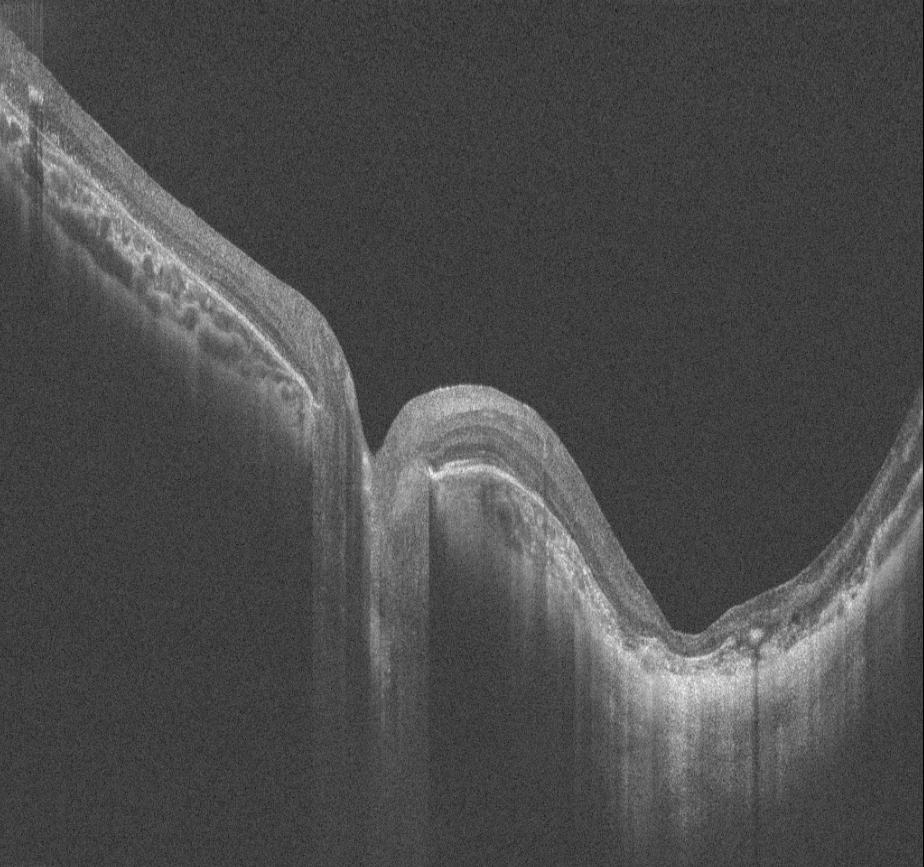

14 yaşındaki erkek hasta bebeklikten bu yana görme kaybı öyküsü ile kliniğimize başvurmuştur. Ailenin tek çocuğudur, anne baba arasında akraba evliliği öyküsü mevcuttur ve her iki gözde görme 1 mps düzeyindedir. Hastanın renkli fundus, FAF ve OCT görüntülerini görmektesiniz. Lütfen cevabınızı aşağıya yazınız.